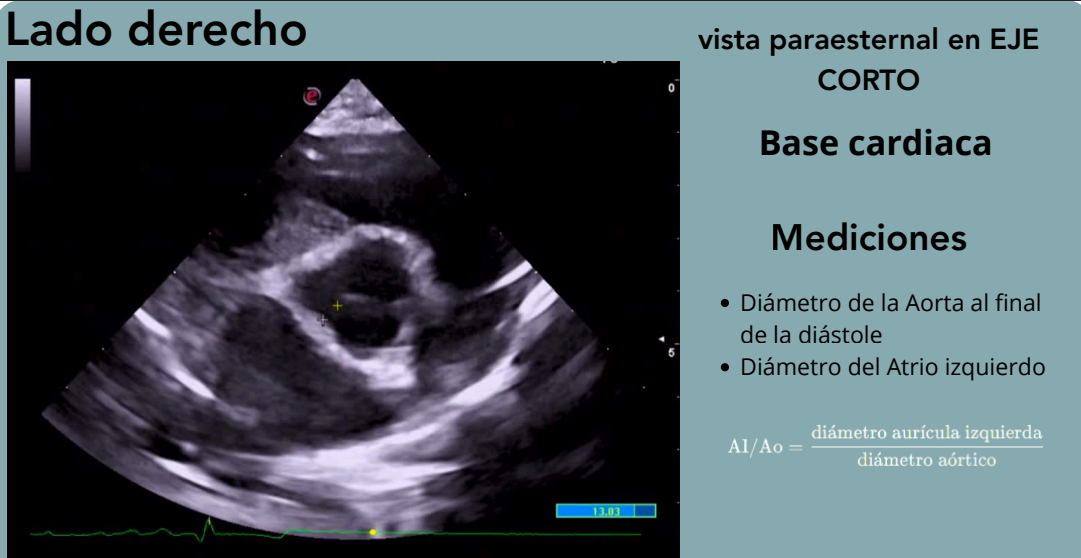

Base cardiaca

Muy bueno para buscar mediciones, interesante para ver la dilatación del atrio izquierdo al compararlo con el de la aorta

El ratio atrio izquierdo/Aorta se mide con la vista paraesternal en eje corto de base cardiaca

Ratio AI/Ao

Relación entre el diámetro de la aurícula izquierda y la aorta.

Permite detectar dilatación auricular.

Valores superiores a 1.5–1.6 indican dilatación significativa.